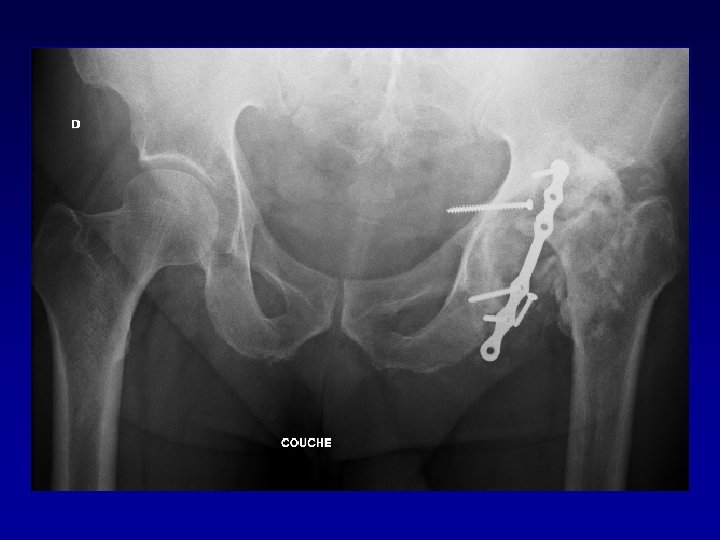

Arthroplastie totale de hanche sur fracture du cotyle complexe Recentrage, reconstruction, orientation du cotyle

Arthroplastie totale de hanche sur fracture du cotyle complexe Recentrage, reconstruction, orientation du cotyle • • Greffe Ostéosynthèse par plaque MK Surtout si pseudarthrose Réduction de la luxation